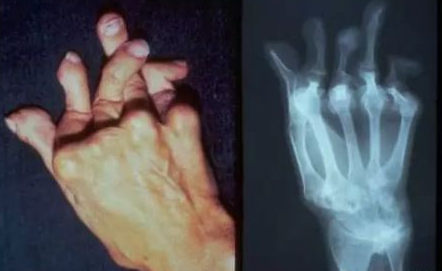

类风湿关节炎最大的危害就是可以治残。因为类风湿关节炎它是一种滑膜炎症,长期的慢性滑膜增生可以导致血管翳形成,血管翳在我们关节内可以逐渐增长,最终可以侵蚀到关节软骨、软骨下骨,导致关节的破坏以及关节间隙狭窄,最终使关节畸形,严重影响到关节功能。郑州治内风湿医院为您讲解:

患者一旦出现重要关节功能的下降或丧失,就可以导致劳动能力下降,郑州治内风湿医院介绍这是因为患者的手腕关节活动会明显受限,正常的关节功能丧失,没有办法进行正常的工作以及生活。严重的晚期类风湿关节炎患者,可以出现全身多个关节的畸形而导致完全丧失生活自理能力,最终瘫痪在床上。